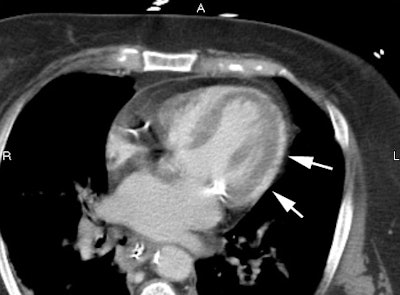

False aneurysms are much less common than true aneurysms. However, a false, or pseudo- aneurysm is a medical emergency as it may rupture at any time. False aneurysms represent a ventricular rupture through the entire myocardial wall that is confined only by adherent pericardium and adjacent epicardial soft tissues [19]. They involve the posterior wall in 50-70% of cases. The lesion results from a occlusion of a dominant right coronary artery in nearly 75% of cases. [ACR Syllabus #40: p.531-535]

Left ventricular pseudoaneurysm: Pseudoaneurysm of the mid free wall of the left ventricle. Note that this is an atypical location - the usual location is inferobasilar/posterior wall. Case from Dr. Scott Flamm. |